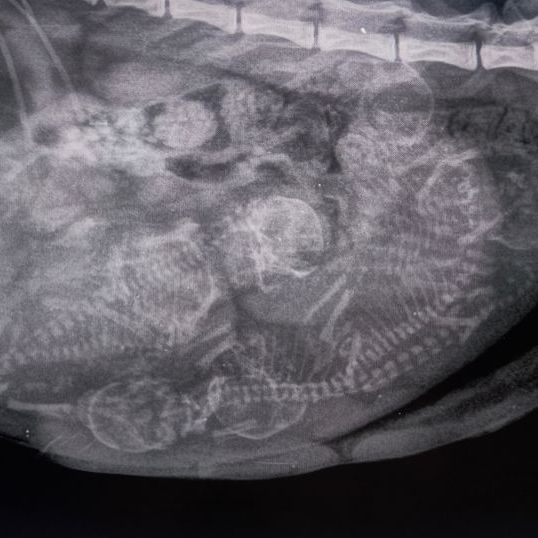

Röntgenbild einer trächtigen Katze. Bald wird die Hobbyzucht Magical Lights Sibirische Katzen und Neva Kitten zu verkaufen haben

Heute war ich mit Heaven beim Röntgen. Ich vermute es werden 6-7 Kitten?